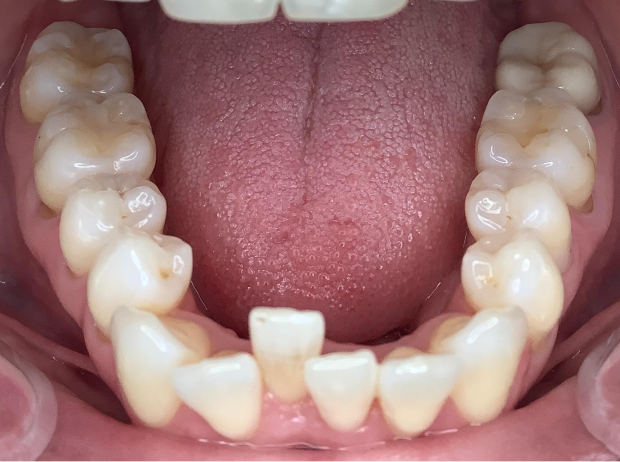

Chief complaint

Fix bottom middle crowding

Resolved Chief Complaint “Straighten my lower teeth”

Developed broad symmetrical arch forms via posterior expansion

Maintained CL I molar and canine relationship

Achieved good posterior occlusion

Uprighted collapsing upper/lower bicuspids

Achieved concentric midlines

Smile Arc esthetically improved

Resolved compromised lower anterior periodontal tissues